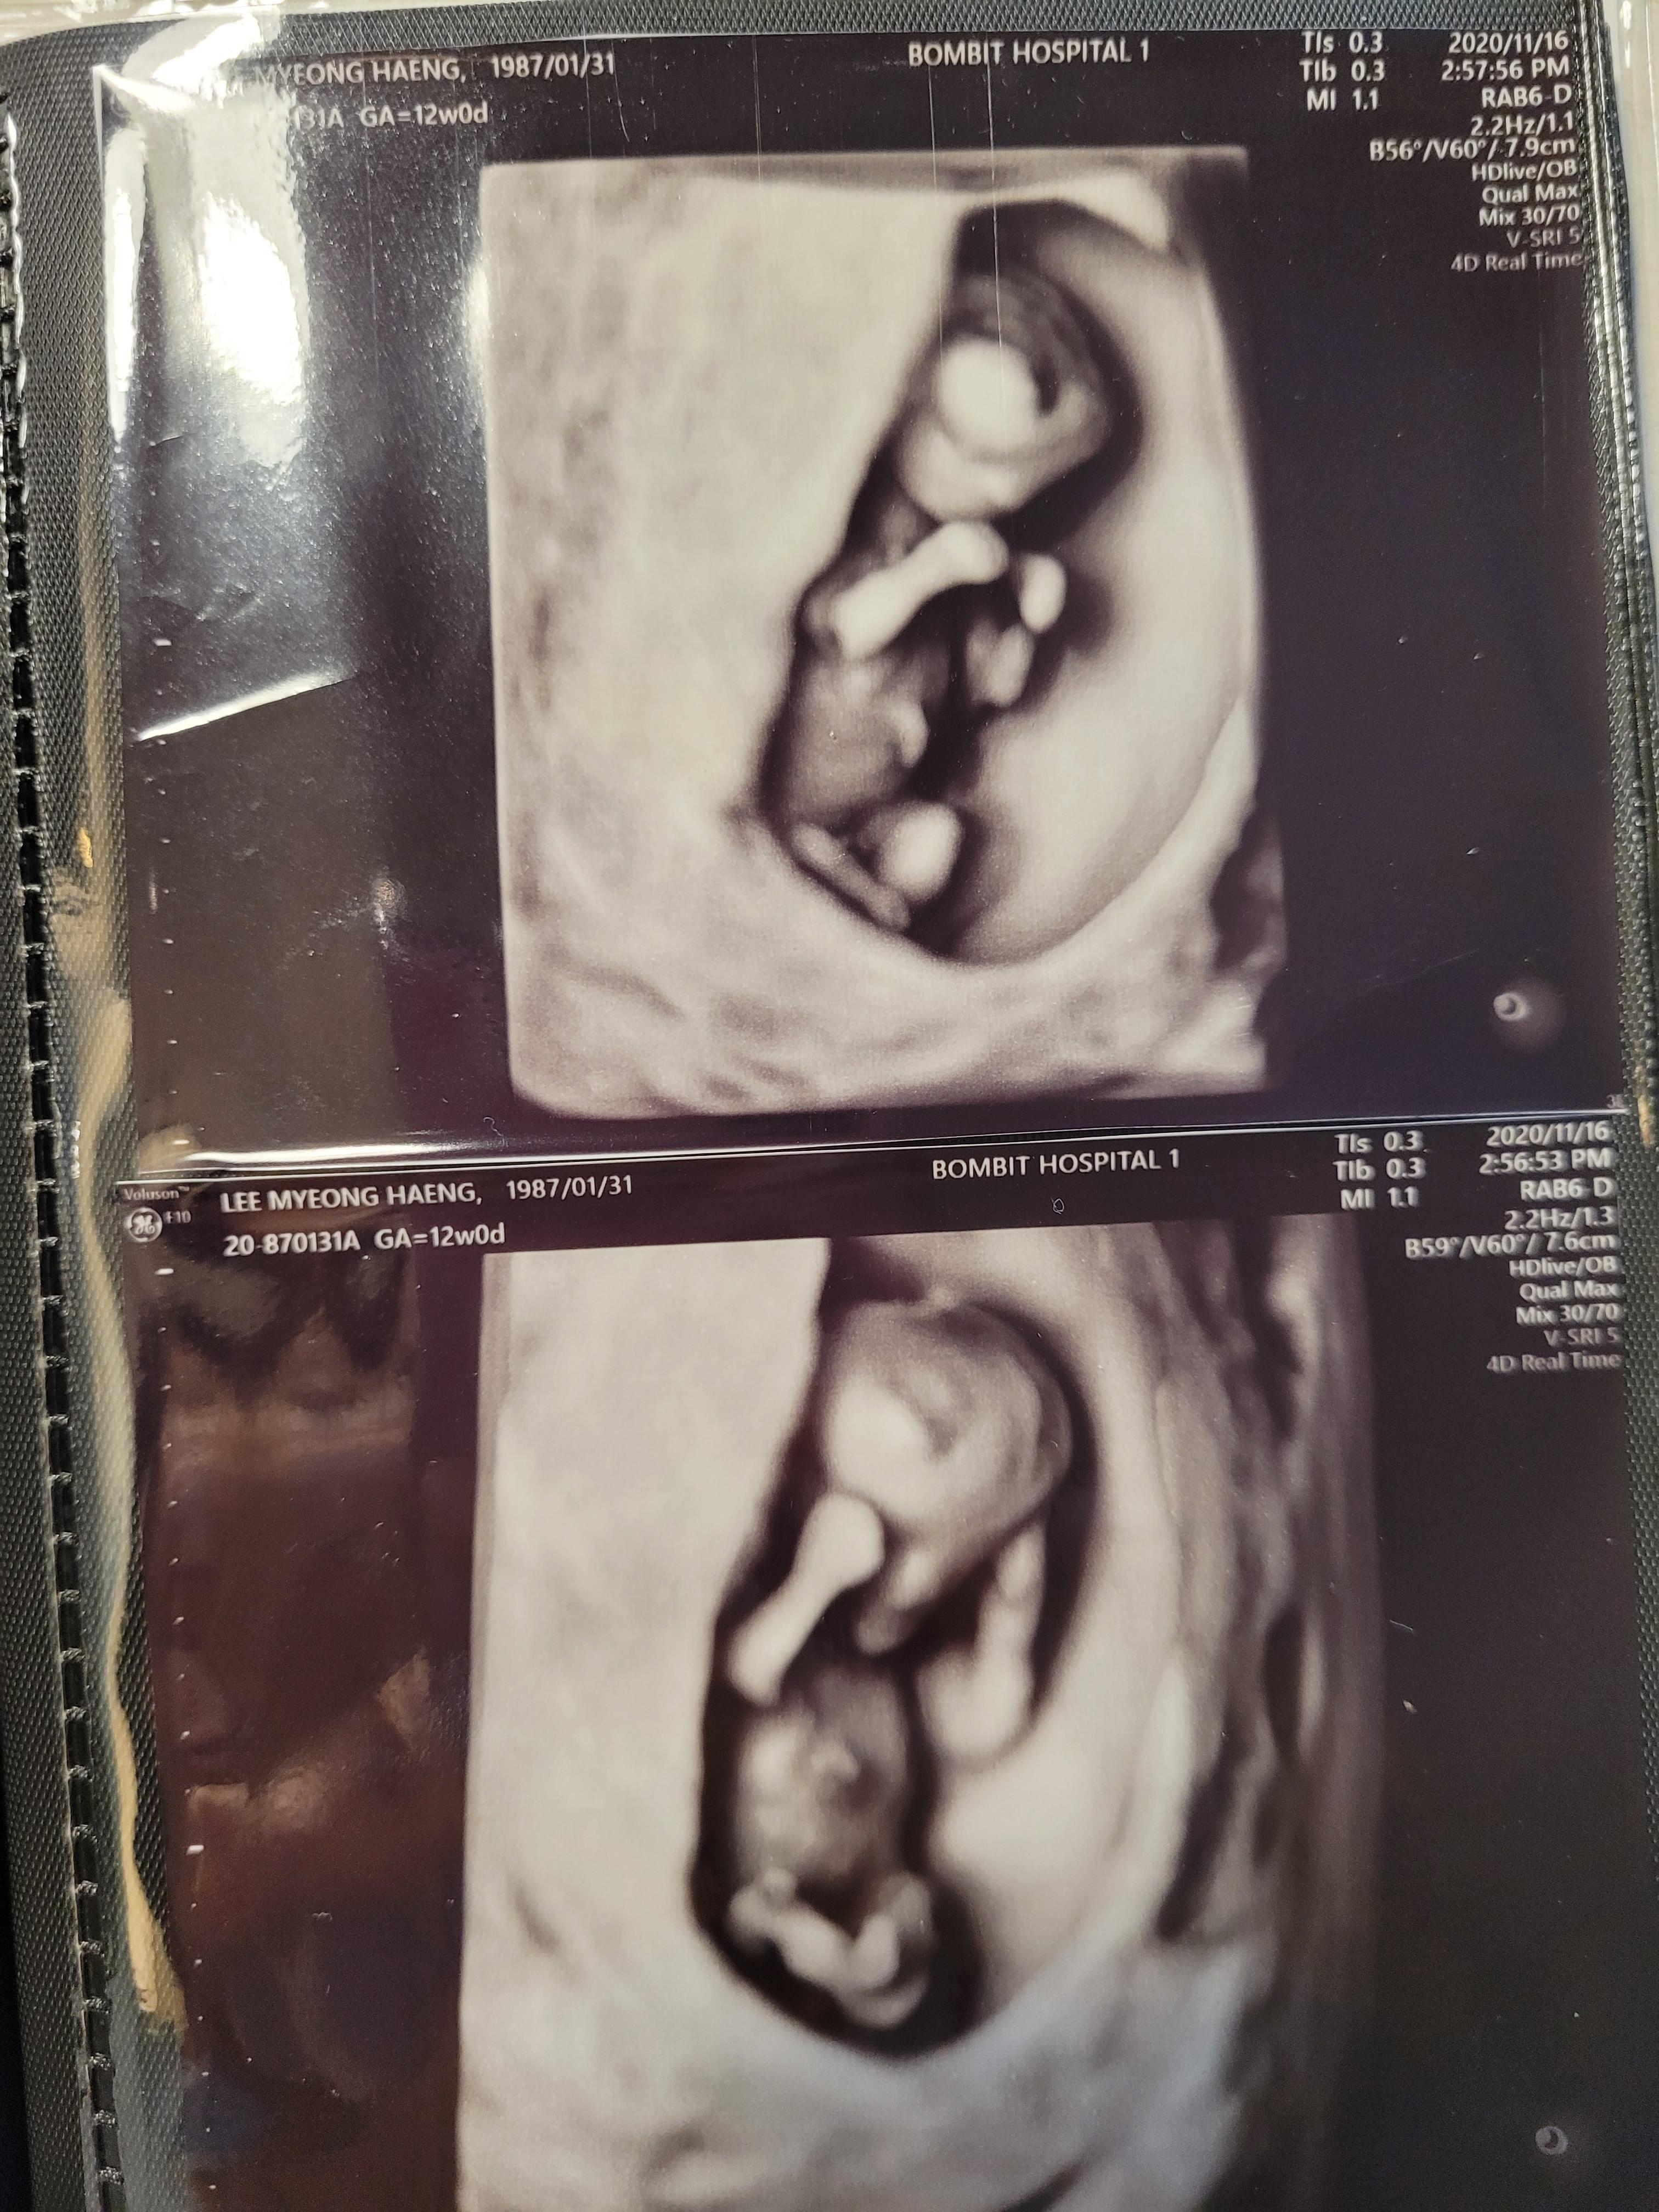

봄빛병원 1차 기형아검사

봄빛병원 입체초음파실은 3층이에요.

저는 늘 2층에서만 진료를 봐서, 3층은 처음 올라갔네요.

이날은 정밀초음파실에서 목투명대를 검사하는데, 입체초음파도 잠깐 봐주십니다.

그리고 아가 얼굴을 보는 입체초음파는 28주쯤 다시해요^^

우리 행복이는 목투명대 0.97cm로, 안전하게 통과했어요. 보통 3cm 이상이면 위험하다고 하는것 같아요.

별일 없겠지~하면서도 검사는 검사인지라 긴장되더라고요.

옆모습도 잘 보여줘서 쉽게 측정하고 끝났어요.

입체초음파로 잠시 아기를 보여주시는데 넘 귀여웠어요.

두 팔을 들고있네요.ㅎㅎ

이날은 얼굴을 자주 가리더라고요. 검사해주시는 선생님 말씀으로는 자는것같다고 하셨어요.ㅎㅎ

입체로보니까 신기하고 귀여웠어요^^